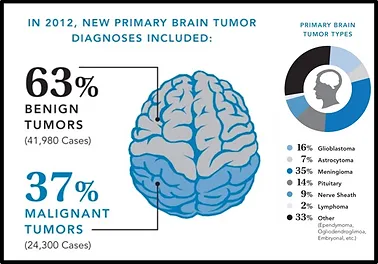

Tümörler iyi huylu (benign) ve kötü huylu (malign) olarak iki ana guruba ayrılırlar. İyi huylu tümörler kanser hücreleri içermeyen gruptur. Genellikle çıkartılabilirler, tekrarlamazlar ve etraftaki normal çalışan dokulara yayılıp onların fonksiyonlarını bozmazlar. İyi huylu beyin tümörlerinin iyi sınırları vardır ve cerrahi ile çıkartılabilirler. Ancak beyin içindeki diğer normal dokulara bası yaparak onların normal çalışmasını engelleyebilirler.

Kötü huylu beyin tümörleri kanser hücreleri içermektedir. Hayatı tehdit ederler. Hızlı büyürler ve etraf normal dokulara yayılarak onların fonksiyon görmesini de engellerler. Genellikle tıpkı ağaçlar gibi etrafa kök salarak beslenmeleri için gerekli olan maddeleri sağlıklı beyin dokusundan çalarak ayakta kalırlar.

Beyin dokusundan kaynaklanan tümörlere birincil (primer) beyin tümörü denilir. İkincil (sekonder) beyin tümörü ise beyin dışı bir kanserin beyne yayılması ile oluşur. Beyin tümörleri kaynak aldıkları dokunun tipine göre adlandırılırlar. En sık görülen birincil beyin tümörü gliomlardır. Bunlar beynin sinir dışı destek hücrelerinden kaynaklanır.